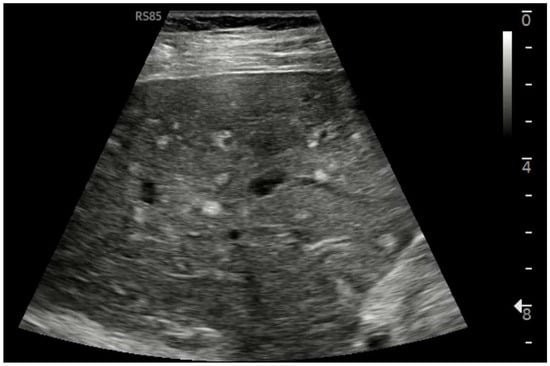

Ultrasound imaging is capable of identifying heterogeneous echotexture and hepatomegaly, which are early indicators of congestive hepatopathy [46]. Several studies have shown correlations between the extent of sonographic abnormalities and the severity of hepatic fibrosis or cirrhosis [36,47,48]. The most common ultrasound findings encompass a nodular hepatic surface, right-lobe volume reduction, smooth-to-rounded contour changes, and irregular outer profiles [49,50,51] (Figure 2). The echotexture appears granular and markedly heterogeneous, with hyperechogenic nodules of varying sizes [49,50,51] (Figure 3, Figure 4, Figure 5, Figure 6, Figure 7 and Figure 8).

Linear Probe (9 MHz) with trapezoidal scan. Diffusely dense and heterogeneous echostructure due to the presence of multiple and diffuse hyperechoic areas, suggestive of peri-portal fibrosis.